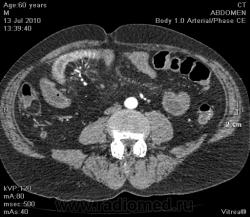

Интересное наблюдение, мужчина 60 лет обследуется у хирургов без малого 2 месяца, с жалобами на интенсивные периодические боли в подвздошной области справа, хирурги пальпируют образование, то увеличивающееся, то уменьшающееся в размерах...

Довольно сложно... Вижу какую то десмопластическую реакцию в брыжейке подвздошной ккишки (фиброзирование, извитость кишки из-за этого), сегмментарное утолщение стенки подвздошной кишки, некоторое расширение сосудов в этой зоне. Межпетельно есть небольшие скопления жидкости. На ум пока приходит фиброзирующий мезентерит или карциноидная опухоль в тонкой кишке с десмопластической реакцией и вторично хронической ишемией за счет этого кишки. Возможно первично все сосудистая патология? А фиброзирование в брыжейке и утолщение стеннки кишки за счет ишемии как результат... Еще вариант - воспалительная псевдоопухоль. А в анамензе не было ли лучевой терапии? А диагноз уже установлен?

По наблюдения возможно не полный перекрут брыжейки подвздошной кишки, частичная тонко-кишечная непроходимость

Женя, полностью с тобой согласен, высказался также, и кстати клиника частичной непроходимости там тоже была, забыл.. ;)

Sclerosing mesenteritis is a disorder of unknown etiology that results in chronic inflammation and fibrosis. Depending on the predominant tissue type within the mass, sclerosing mesenteritis can be subgrouped as: (a) mesenteric panniculitis (inflammation); (b) mesenteric lipodystrophy (fat necrosis); or (c) retractile mesenteritis (fibrosis), as seen in this case. This disorder is usually confined to the mesentery and can occasionally calcify. By CT, retractile mesenteritis presents as a soft tissue mass that can contain fat and calcifications extending from the root of the mesentery towards the small bowel. This can lead to retraction and kinking of the bowel, resulting in crampy abdominal pain. The bowel wall thickening in this case is due to venous or lymphatic congestion. Carcinoid tumor arising in the small bowel can have mesenteric metastasis causing desmoplastic reaction, calcifications, and bowel kinking similar to retractile mesenteritis. This would be the best differential diagnosis in this example. Other entities that can involve the mesentery include lymphoma, metastases, and sarcomas. These do not usually calcify or cause bowel obstruction.

"Склерозирующий мезентрит - это заболевание неизвестной этиологии, исходом которого является хроническое воспаление и фиброз. В зависимости от преобладающего типа ткани в образовании, склерозирующий мезентрит подразделяетя на: a) мезентериальный панникулит (воспаление) b) мезентериальная липодистрофия (жировой некроз) с) ретрактильный мезентерит (фиброз), как в данном случае. Заболевание чаще всего ограниченно брыжейкой тонкой кишки, и иногда кальцифицируется. На КТ ретрактильный мезентерит представляется собой мягкотканной плотности образование, которое может содержать жир и кальцификацию, распространяющееся со стороны корня брыжейки тонкой кишки по направлению к тонкой кишке. Это может приводить к ретракции и кинкингу (извитости) тонкой кишки, что проявлется спастическики болями в животе. Утолщение стенки тонкой кишки в этом случае является результатом венозного и лимфатического застоя. Карциноидная опухоль тонкой кишки может сопровождаться метастазами в брыжейку тонкой кишки вызывая десмопластическую реакцию, кальцификацию и извитость тонкой кишки (изменения такие же как и при ретрактильном мезентерите). Это будет являтся лучшим диф.диагнозом в данном случае. Другие процессы, которые могут вовлекать брыжейку включают в себя лимфому, метастазы и саркому. Они обычно не кальцифицируются и не вызывают непроходимости тонукой кишки"

Теперь немного покртиткую свои версии: на мезентерит - как то маловато поражен корень тонкой кишки (то есть обычно при мезентерите поцесс идет с корня, тут же процесс более локализован в дистальной части брыжейки) + тонкокиш.непроходимость и жидкость межпетельно жля этого процесса не свойственна (даже с учетом застоя).  Далее для карциноида - хотелось бы все таки чтобы в артериальную фазу была видна опухоль (она была бы гиперденсной). Если расчитывать что процесс в брыжейке мтс от карциноида, то : во-первых - маловата десмопластическая реакция, во-вторых - не видно чтобы были увеличены лимфоузлы рядом, в 3-их - обычно метастазируют карциноиды >10мм (то есть хотелось бы все таки видеть первичную опухоль в артериальную фазу).

Ну и последнее - свободная жидкость межпетельно в бр.полости - больше в пользу тонкокиш. непроходимости.  Причина - возможна та - которую называл коллега rentgengb, возможно сосудистого харрактера, возможно за счет воспалительного процесса какого-то в кишке. Вообщим будем надеятся что что-то прояснится. Будем ждать результатов, спасибо Сергей Сергеевич за интересный случай.